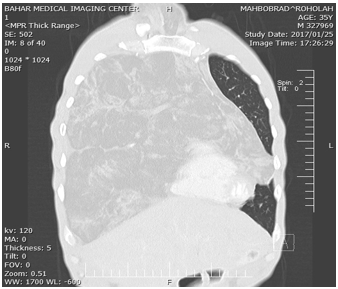

Figure 2: Showing Sagittal CT scan of chest showing a mass to occupying total right hemithorax andand extend to left hemithorax and neckwith strands and islands of soft fatty tissue.

Haematological and serological investigations, including tumor markers (alphafetoprotein, lactate dehydrogenase, beta human chorionic gonadotrophin, and alkaline phosphatase) were normal and not contributory to the diagnosis. With these radiologist report, the patient underwent to US-needle biopsy identified atypical cell and suspicious to liposarcoma. On completion of the preoperative evaluation, a right extensive posterolateral thoracotomy was performed via the fifth intercostal space. a large, encapsulated, vaguely lobulated mass was found within the anterior mediastinum. The mass arose in the anterior mediastinal fat, increasing in size as it extended above to the right side of neck and to the superior vena cava to the right inferior pulmonary vein, and extended to left hemithorax, compress the heart, diaphragm and shifted the mediastinum to the left, The mass occupied approximately 90% of right and 30% of left pleural cavity, resulted in marked compression and totally collapsed of right lung and partially collapse of left upper lobe (Figure1-4).